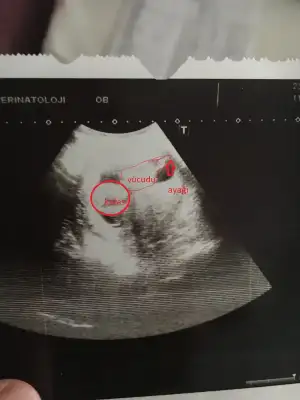

Resim yükledim kızlar ama ben bu usg Fotoğraflarından hiç bişi anlamıyorum başını poposunu bile ayıramıyorum ki nerde cinsiyet tahmini anlayanlardan yorum bekliyorum

Aynı dertten bende de var da o yüzden sordum,Turgut Özal Hastanesi var burda önceden özel hastaneydi,sonradan devlete geçti,ama hastanenin içi on numara filan,ben de oraya Gebe Okuluna gittim ,gitmişken bir de bebeğimi kontrol ettiriyim dedim,ultrasyon ile baktılar,ultrasyon kağıdı verince de şaşırdım hatta ,vermiyorlar zannediyordum.Keşke almasaydım ,bebeğin nerde olduğunu bile anlayamadım ,anlayan varsa bana da desin :KK70:

kafayı ve ayakları gördüm sanki :KK70: